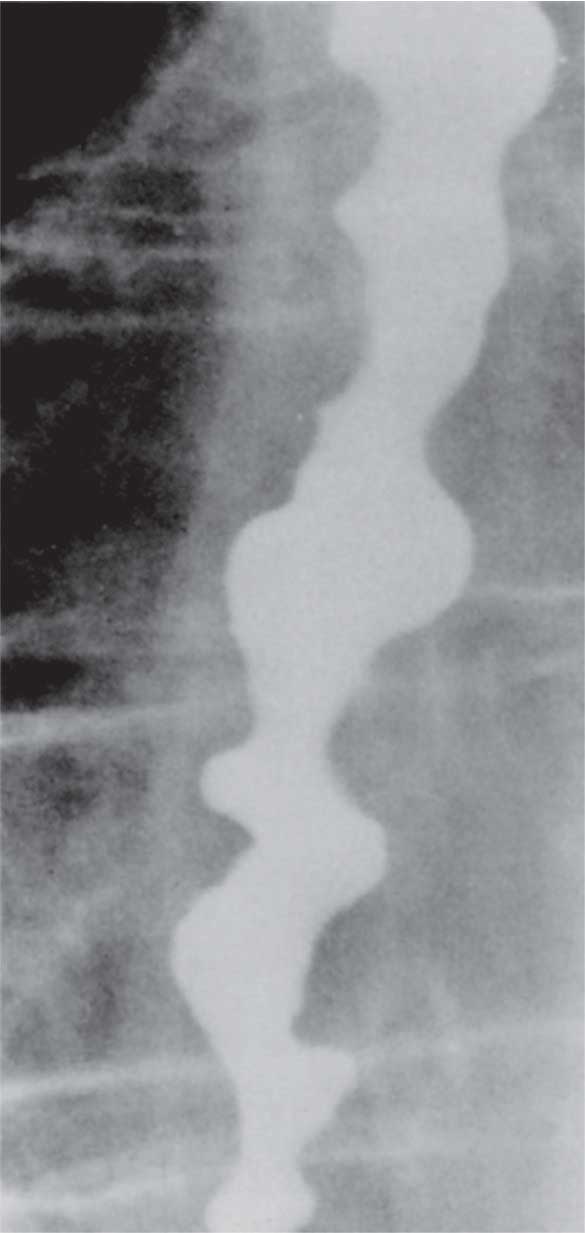

1- تصوير المريء الظليل: تختلف المظاهر الشعاعية المشاهدة بتصوير المريء الظليل من مريض إلى آخر. يشاهد في كل المرضى غياب الحركات التمعجية للمريء. يتوسع جسم المريء تدريجياً ليصبح متعرجاً مع ركودة تشمل الأطعمة والمفرزات. لا ينفتح القسم السفلي من المريء بشكل تام ويأخذ القسم النهائي من المريء شكلاً يشبه منقار الطير.

| الشكل (3) مظهر وصفي لتشنج المريء المعمم بصورة المريء الظليلة يظهر مريئاً بشكل السبحة أو البرغي |